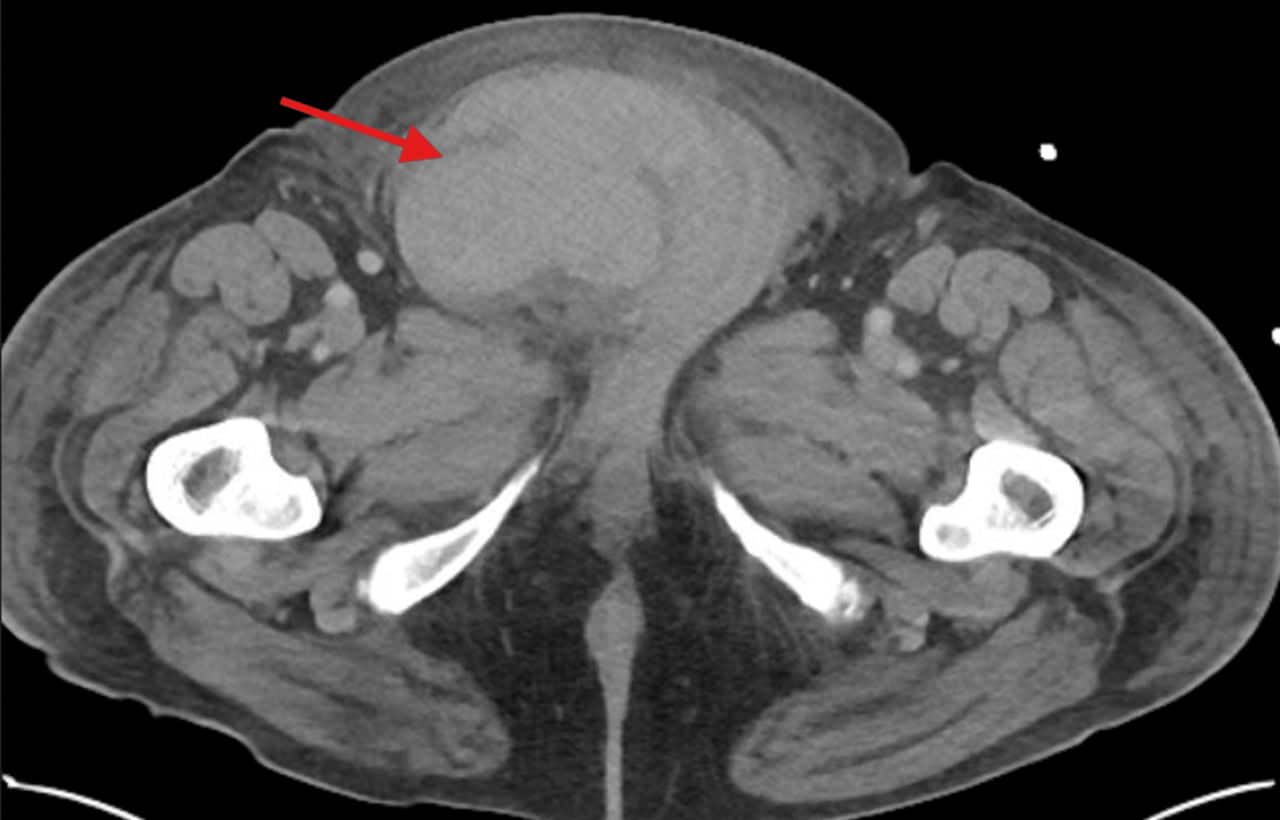

Комплексное обследование, включая КТ, выявило спонтанный разрыв правого яичка с формированием обширной гематомы. В ходе экстренной операции поврежденный орган пришлось удалить из-за массивного кровотечения. Параллельно у пациента диагностировали комплекс кардиологических патологий: декомпенсированную сердечную недостаточность, легочное сердце, аневризму аорты и инфаркт миокарда без подъема сегмента ST.